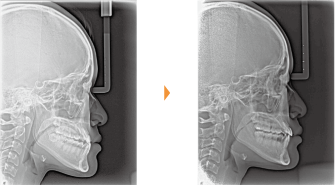

| 主訴 | 前歯が出ている |

| 年齢・性別 | 35歳 / 女性 |

| 治療方針 | 叢生も前歯の突出も大きいケース。小臼歯抜歯だけでは改善できないため、大臼歯の抜歯も行なった。 |

| 抜歯部位 | 上下顎左右小臼歯、左上第1大臼歯(計5本) |

| 使用装置 | マルチブラケット装置 |

| 治療期間 | 36か月 |

| リテーナー | 上顎インビジブル、フィックス、下顎インビジブル |

| 費用 | 885,000円(税別) |